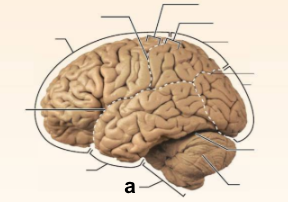

Identify the structure labeled “a” in the image.

Brain Stem

Identify the structure labeled “b” in the image.

Central culcus

Identify the structure labeled “c” in the image.

Cerebellum

Identify the structure labeled “d” in the image.

Frontal lobe

Identify the structure labeled “e” in the image.

Lateral sulcus

Identify the structure labeled “f” in the image.

Occipital lobe

Identify the structure labeled “g” in the image.

Parietal lobe

Identify the structure labeled “h” in the image.

Parieto-occipital sulcus

Identify the structure labeled “i” in the image.

Postcentral gyrus

Identify the structure labeled “j” in the image.

Precentral gyrus

Identify the structure labeled “k” in the image.

Temporal lobe

Identify the structure labeled “l” in the image.

Transverse cerebral fissure